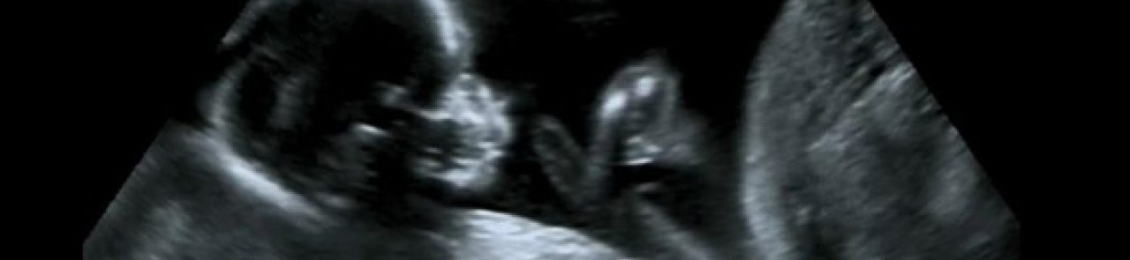

فحص السونار المهبلي هو إجراء روتيني آمن وشائع الاستخدام من قبل افضل دكتور اشعة في المدينة المنورة لعمل السونار وفحص نبض الجنين حيث أن ذلك يساهم اثناء الفحص في الكشف عن نبض الجنين وكذلك التشخيص الدقيق لمجموعة متنوعة من المشكلات الصحية لدى النساء بشرط أن يتم تنفيذه بدقة واحترافية هذا ما يوفره مجمع الطب المتميز […]

تساءلت بعض السيدات على مين عملت تحديد نوع الجنين ونجحت بذلك مع مجمع الطب المتميز بالمدينة المنورة، وفي الحقيقة أن المركز يقدم جميع عمليات تحديد الأجنة من خلا لافضل دكتور نساء في المدينة المنورة قادرة على إنجاح الأمر بسهولة باستعمال أدق وأحدث الأجهزة، بالإضافة إلى ذلك يقوموا بتقديم كافة الاستشارات والمعلومات والتفاصيل التي تعمل على […]